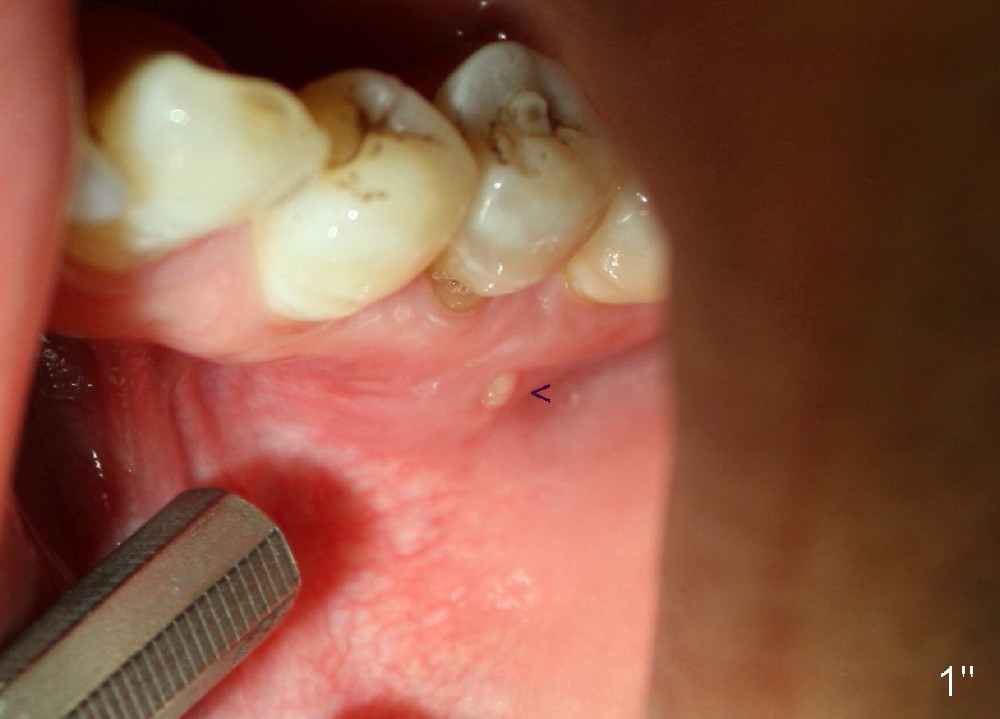

A 40-year-old Chinese man has periodic (once a month) mild pain and swelling in the lower left quadrant. Clinical exam reveals dens evaginatus (Fgi.1': <) in #20. Upon pressure from mouth mirror handle, there is limited amount of purulent discharge from the fistula (Fig.1": <). Preop PA shows a large canal with large periapical radiolucency (Fig.1). RCT started on Aug 6, 2010 with #70 file at 20 mm (Fig.2), #120 file at 16 mm (Fig.3) and CaOH paste in the canal (Fig.4). The dressing changed on Oct 8, 2010 (Fig.5). RCT finished on Jan 25, 2011 with master cone (rolled with several gutta perchae) (Fig.6), lateral condensation (Fig.7) and after vertical condensation and build-up (Fig.8). The canal was wet in the last two appointments with no sign of apexification. Follow up is done in 7 months (Fig.9), 11 months (Fig.10) and 18 months. Although the patient reports no pain after the treatment, the fistula remains with purulent discharge. The patient does not accept apical surgery. What should we do? Retreat with MTA (1,2,3)?